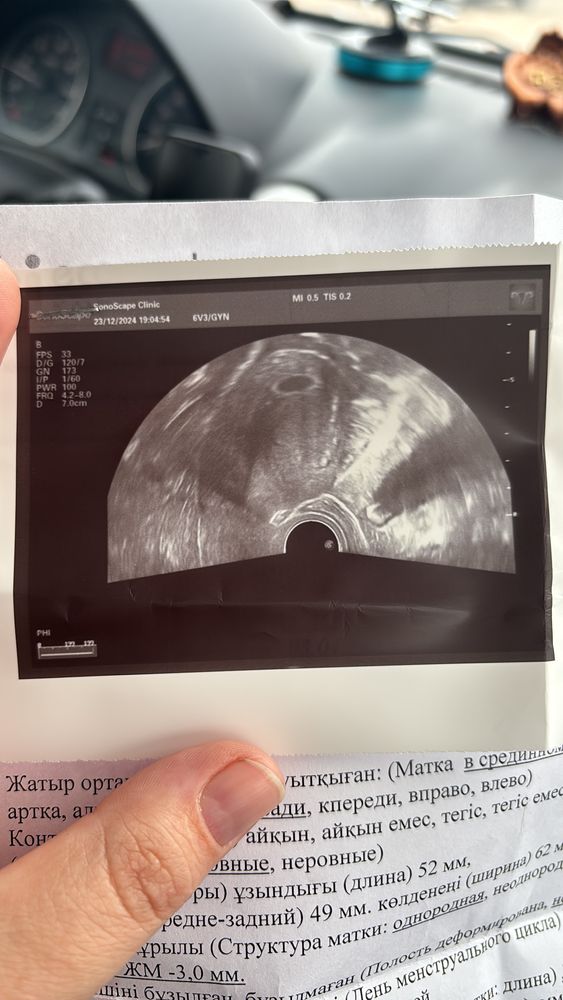

Арина Кусаинова, очень рада за вас! У меня тоже на 21 день кровянистые выделения и сказали пить тренакса, сделали узи сказали беременность 5-6недель. выделения прекратились но теперь переживаю🙈через 2 недели узи на сердцебиение, время теперь будто остановилось, покой и лежать сказали